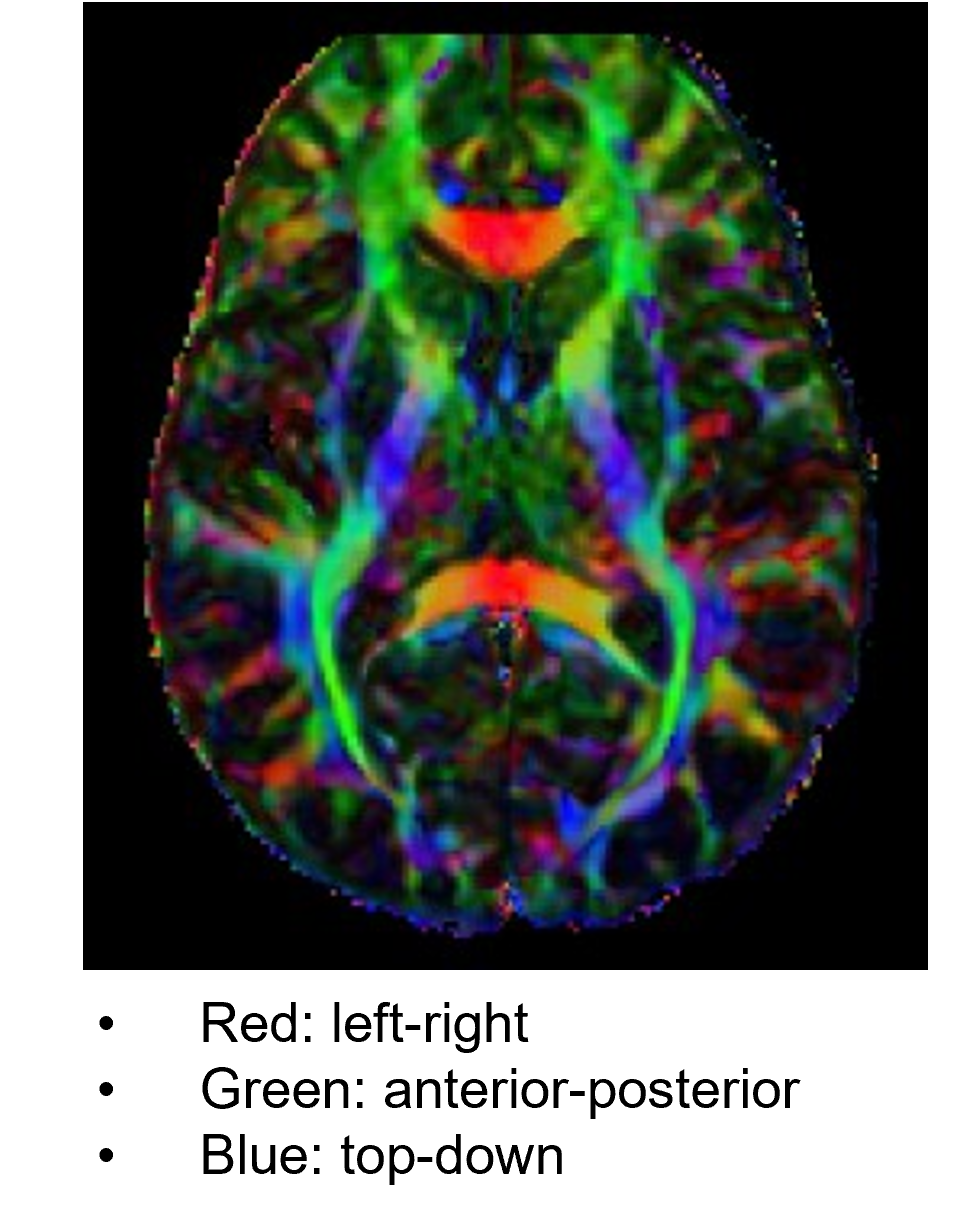

DTI is an MRI method that images fiber pathways by detecting directional movements of water molecules in ventricles. Movement of water molecules in nerve fibers tends to follow the longitudinal axis, a property called fractional anisotropy (FA). With DTI, we can detect degeneration of axons and distortion of and damage to fibers.

The information of white matter fiber tracts obtained from DTI can be also analyzed in combination with T1w/T2w MRIs, fMRI, and EEG/MEG measures. DTI images are often displayed in R-G-B colors representing strengths of different directional tensors. DTI is one of the central MRI measures of Human Connectome Project (HCP).